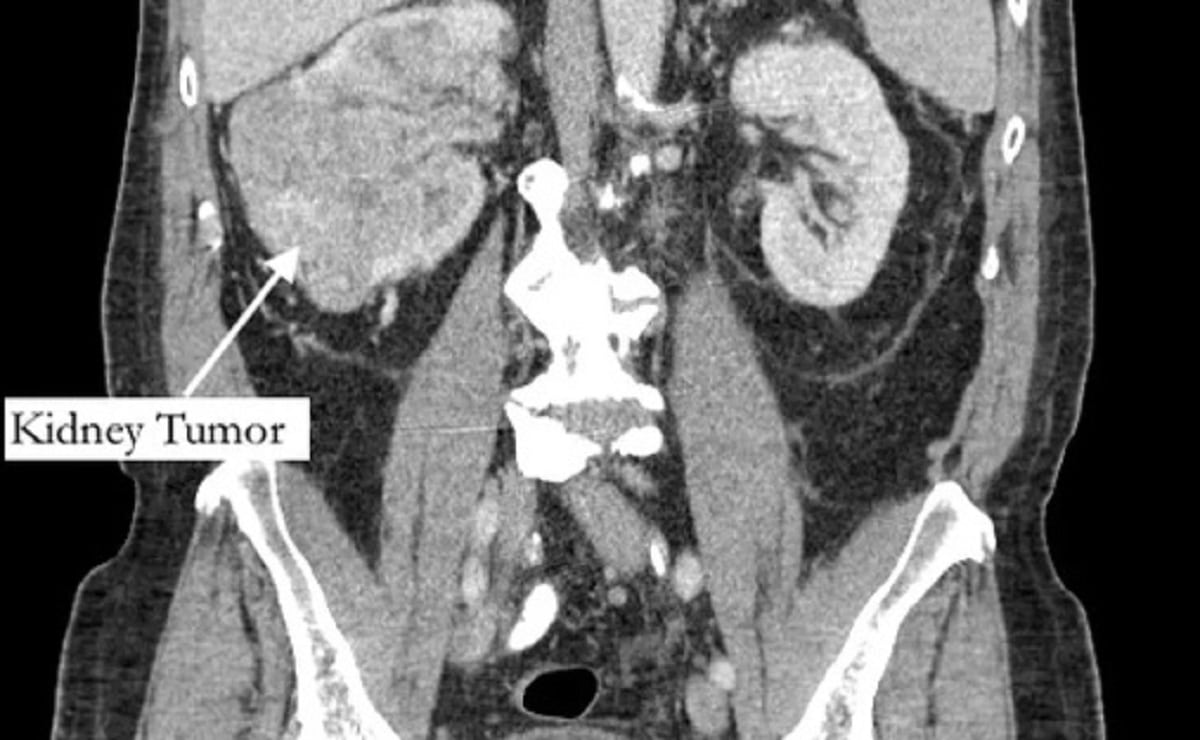

Segundo o jornal “New York Post”, ele sentia a dor havia cinco anos, e pensava que se tratava de uma fratura, mas recebeu o diagnóstico de grande tumor no rim e de um trombo tumoral, um tumor que se estende até um vaso sanguíneo.

No entanto, os sintomas começaram a aumentar. A dor subiu para o tornozelo e, em março deste ano, sua perna começou a inchar. Foi só aí que um médico pediu um exame abdominal, que revelou o tumor.

O exame, encaminhado a um urologista, identificou ainda um trombo (coágulo no sangue) que cresceu através da veia renal e preenchia a veia cava, que drena sangue para o coração, e tinha 99% das artérias da coronária bloqueadas, além do fígado quase entrando em falência.